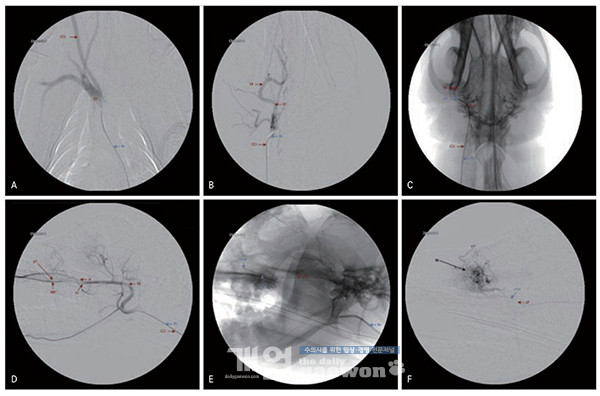

비강 색전술의 과정은 우선 환자를 마취 후에 대퇴동맥을 절개하여 접근하게 된다. 카테터와 와이어를 통해 maxillary artery로 접근하고, 혈관 조영을 하게되면 크게 3가지 동맥의 분지(infraorbital artery, sphenopalatine artery, major palatine artery)가 확인 된다[그림 1].

확인된 혈관은 다양한 두부 장기에 혈류 공급을 하고 있어 종양의 영양 동맥(feeding artery)이 되는 혈관에 대해 미리 판단하게 된다. 때에 따라서는 색전 형성으로 인해 눈물샘의 파괴, 피부괴사 등의합병증이 발생할 수 있으며, 만약 색전물질이 역류될 경우엔 다른 안면 장기의 허혈, 심한 경우 뇌경색까지 발생할 수 있어 사전에 정확한 혈관 해부에 대한 이해가 필요하다.

다른 종양 인터벤션과 마찬가지로 종양의 feeding artery로 마이크로카테터를 삽입하여 색전물질을 주입하게 된다. 일반적으로 PVA particle 또는 gelatin sponge particle 등이 색전물질로 이용되며, 필요에 따라 사전에 항암제 주입이 추천될 수 있다.